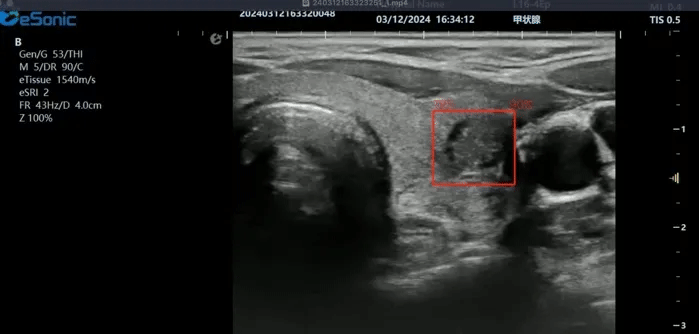

hjc888黄金城官网医疗(ESI)表示,其最新的人工智能功能可以帮助到医疗机构的工作效率,功能包括,实时、动态、快速自动识别病灶,良恶性病灶概率预测,甲状腺结节和乳腺的二维灰阶动态自动实时检测需求,提供多个结节动态检测轮廓框。实时获取多幅具备临床特征(大小、属性等)的结节切面,同时提供当前切面所示结节的结节大小、属性特征、TI-RADS 分级。

对于甲状腺结节相关的自动检测功能,甲状腺结节病灶检出率≥95%,良恶性分类灵敏度≥90%、良恶性分类特异度≥85%。